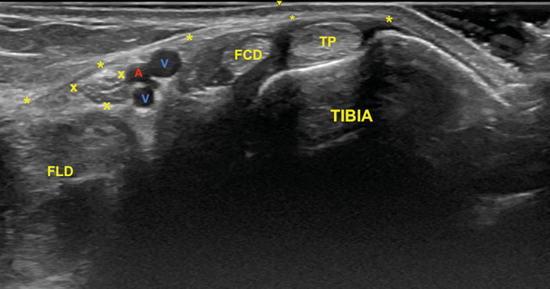

El examen para localizar la división del nervio tibial continúa desplazando la sonda en eje transverso y en sentido cráneo caudal desde la posición anterior (Figura 4) en busca del túnel del tarso distal o túnel talocalcáneo (Figura 10), donde el nervio se divide en el nervio plantar medial y nervio plantar lateral (Figura 11), 1.3 a 2.5 cm proximal a la división de la arteria tibial posterior3,9. Dellon-Mackinnon describieron la división del nervio tibial en relación al eje entre el centro del maléolo medial y la tuberosidad del calcáneo (línea Dellon-Mackinnon) (Figura 12) en un 90 % de los casos (55 % en la línea, 16 % 1 cm distal y 19 % 1 cm proximal)10. Más tarde, Moroni y cols. refieren tal división 16.4 mm proximal a dicho eje8.

Figura 11. Imagen sonográfica de la diferenciación del nervio plantar medial (M) y del nervio plantar lateral (L) debajo de la arteria y venas (A, V) y sobre el tendón flexor largo del primer dedo (FLD). En superficie el retináculo flexor (*).

No obstante, la visualización de los nervios plantar medial y plantar lateral es más evidente cuando se avanza hacia distal. Para ello se mantiene la sonda en eje corto (Figura 13) tomando como referencia la tuberosidad posterior del calcáneo, de donde parten el eje de Dellon-Mackinnon4 y el triángulo de Heimkes (área entre tuberosidad del calcáneo, el vértice del maléolo medial y el navicular)8 (Figura 12).

La imagen sonográfica se centrará en el espacio situado bajo la fascia profunda del músculo abductor del primer dedo, por donde discurrirán los haces neurovasculares plantar medial y plantar lateral, diferenciados y separados por el septo de Heimkes o interfascicular3. El nervio plantar medial se muestra con mayor sección que el nervio plantar lateral, y las venas laterales con mayor luz que las mediales (Figura 14).